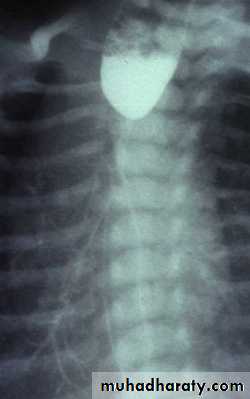

Achalasia continue

5. DILATATION (Sac like in proximal part )6-Undulating or spiky out line due to sluggish peristalsis.

7 Non- homogeneity of Barium due to food particles.

8-Air Barium level.

9- CXR shows widening of mediastinum.

10-Absence of fundal gas shadow.

7-Basal fibrosis in lungs due to repeated aspiration pneumonia .

LEFT: Dilated esophagus (arrows) appears as long, well-defined structure paralleling heart RIGHT: Dilated esophagus usually deviates to right. Narrowing (arrow) at hiatus.